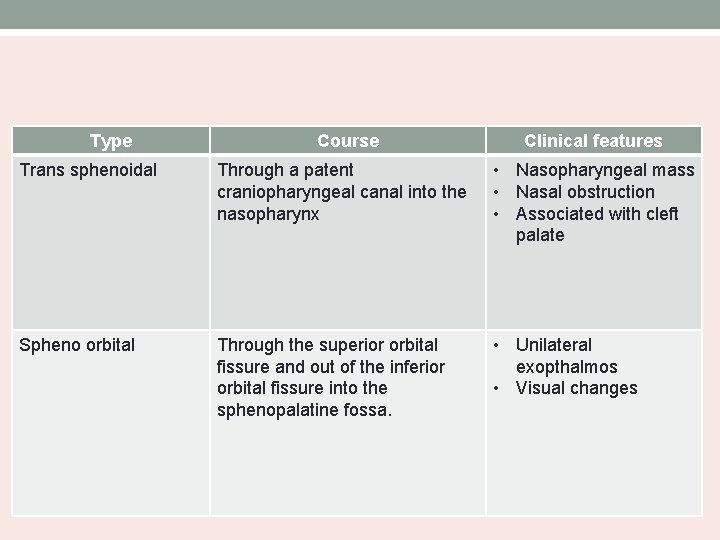

Type Course Clinical features Trans sphenoidal Through a patent craniopharyngeal canal into the nasopharynx • Nasopharyngeal mass • Nasal obstruction • Associated with cleft palate Spheno orbital Through the superior orbital fissure and out of the inferior orbital fissure into the sphenopalatine fossa. • Unilateral exopthalmos • Visual changes